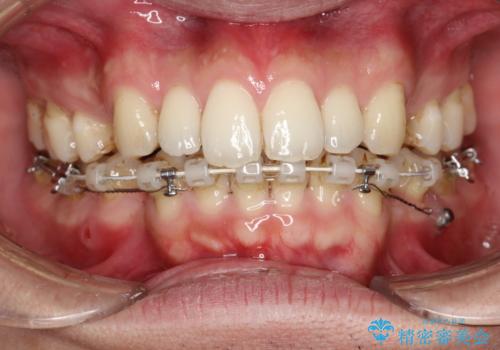

前歯の隙間を閉じたい 口元も下げたい ハーフリンガルによる抜歯矯正

- 上の前歯の隙間と口元を下げたとのことで来院されました。

上顎正中離開と、口唇の突出感がありました。

上下左右の歯を1本ずつ抜歯しして、上顎の前歯を後方に移動させるのと、正中の隙間を閉じる計画としました。

装置はなるべく目立たないものをご希望でしたので、ハーフリンガルを選択されました。